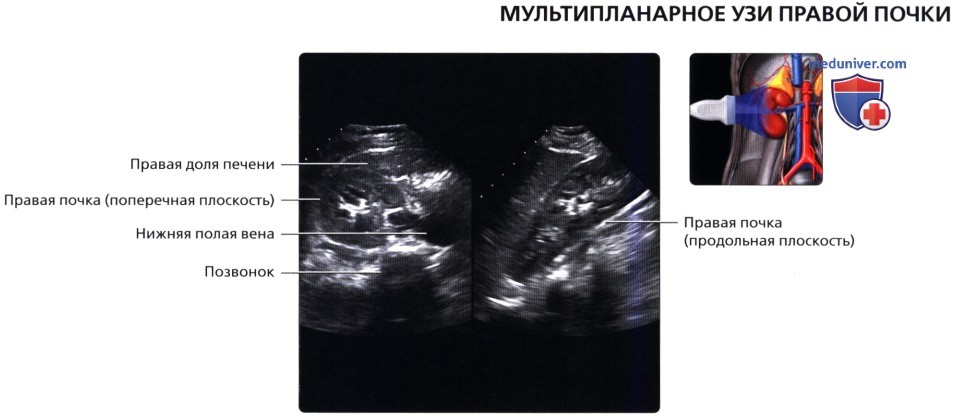

Сначала исследуют почки в продольном направлении (поясничная область), затем изучают поперечные и косые срезы, перемещая датчик на переднюю и боковые поверхности живота. При этом пациента просят поочередно повернуться на правый и левый бок. Такая техника позволяет определить локализацию (месторасположение) почек, их размеры и форму, оценить состояние паренхимы, почечных синусов, чашечек и лоханок.

Для определения подвижности почек и улучшения визуализации органов при каждом изменении положения тела врач просит больного вдохнуть и на несколько секунд задержать дыхание. На вдохе почки опускаются из-под реберной дуги и просматриваются намного лучше. УЗИ почек стоя делают при подозрении на нефроптоз (опущение одной или обеих почек).

• Забрюшинные структуры бобовидной формы с четким контуром, смещающиеся при дыхании

• Правая почка:

о Печень используется в качестве акустического окна

о Датчик устанавливается в подреберье или в межреберный промежуток

о Выполняйте исследование при различной глубине вдохе

о Попросите пациента немного повернуться влево, приподняв правый бок и выполняйте сканирование с боковой/заднебоковой поверхности

• Левая почка:

о Ее труднее визуализировать из-за газа в тонкой кишке и в селезеночном изгибе ободочной кишки

о Обычно левую почку проще визуализировать, используя заднебоковой эхографический доступ и попросив пациента немного повернуться вправо приподняв левый бок

о В сложных случаях полностью переверните пациента в положение лежа на правом боку, подложите подушку под его правый бок и попросите его поднять левую руку над головой:

— Для исследования верхнего полюса левой почки можно использовать селезенку как акустическое окно